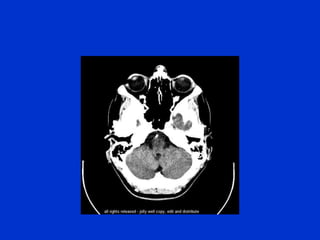

The document provides an overview of normal brain anatomy including key structures like the central sulcus, lateral sulcus, white matter tracts, brain stem, ventricular system, and basal cisterns. It was authored by Dr. Maliha Fansur, Assistant Professor at SIMS/SHL, who appears to have expertise in neuroanatomy.